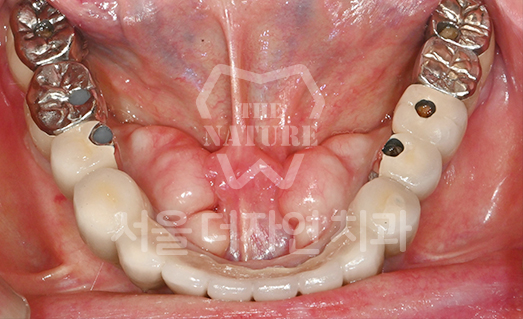

전체 임플란트

전체적으로 치아를 회복하기 위한 임플란트

치아의 기능을 다시 회복하기 위해

선택하는 임플란트입니다. 상실한 치아를 오랫동안 방치한 경우

상, 하악 잇몸뼈의 양도 부족한 경우가 많기 때문에 개개인의 건강 상태를 고려하여

정확한 수술 계획을 세워야 합니다.

• BEFORE: 2022.12.15

• AFTER: 2023.02.23